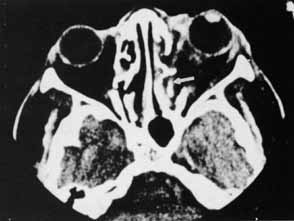

Fig. 12 In this patient (A) with right medial wall and tripod fracture, the mass effect of orbital air (B) (arrow) causes exophthalmos and contributes to hypophthalmos.